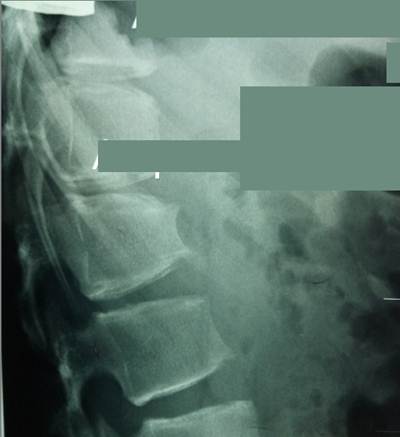

Фрагмент

боковой рентгенограммы позвоночника девушки 17 лет, демонстрирующий последствия

юношеского остеохондроза по завершении костного роста. Наблюдается деформация

тел позвонков, «искусанность» их краев, нарушение формы межпозвоночных

пространств, что соответствует изменениям в межпозвоночных дисках. Клинические проявления столь ярких рентгенологических

изменений отсутствовали. Вполне

возможно, что они разовьются с возрастом.